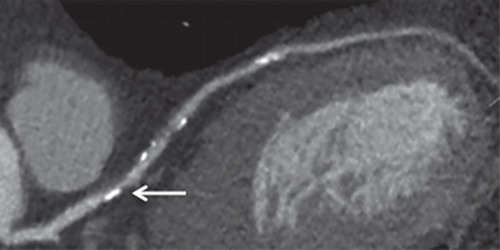

Ateroesclerosis coronaria subclínica y riesgo de infarto de miocardio

En este estudio de cohortes realizado en Dinamarca, en personas asintomáticas, la detección de aterosclerosis coronaria obstructiva subclínica por medio de angiografía coronaria con TC se asoció con un riesgo más de 8 veces mayor de infarto de miocardio. Annals of Internal Medicine, 28 de marzo de 2023.